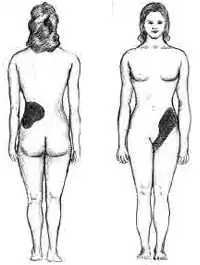

Клиническая картина

Местная симптоматика:

- Боли в поясничной области на стороне поражения. При необструктивных пиелонефритах обычно боли тупые, ноющего характера, могут быть низкой или достигать высокой интенсивности, принимать приступообразный характер (например, при обструкции мочеточника камнем с развитием т. н. калькулёзного пиелонефрита).